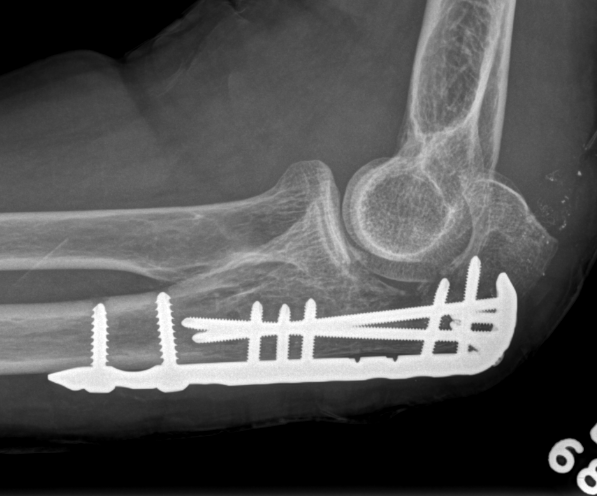

ORIF with olecranon plate

Indication

Fracture distal to center of rotation of elbow / trochlea

Technique

Lateral decubitus with tourniquet

- curvilinear incision to avoid prominence of olecranon

- identify and protect ulna nerve

- reduce fracture with arm in extension

- ensure articular congruity

- use anatomical precontoured plate

- may want to split distal triceps to reduce proximal plate prominence